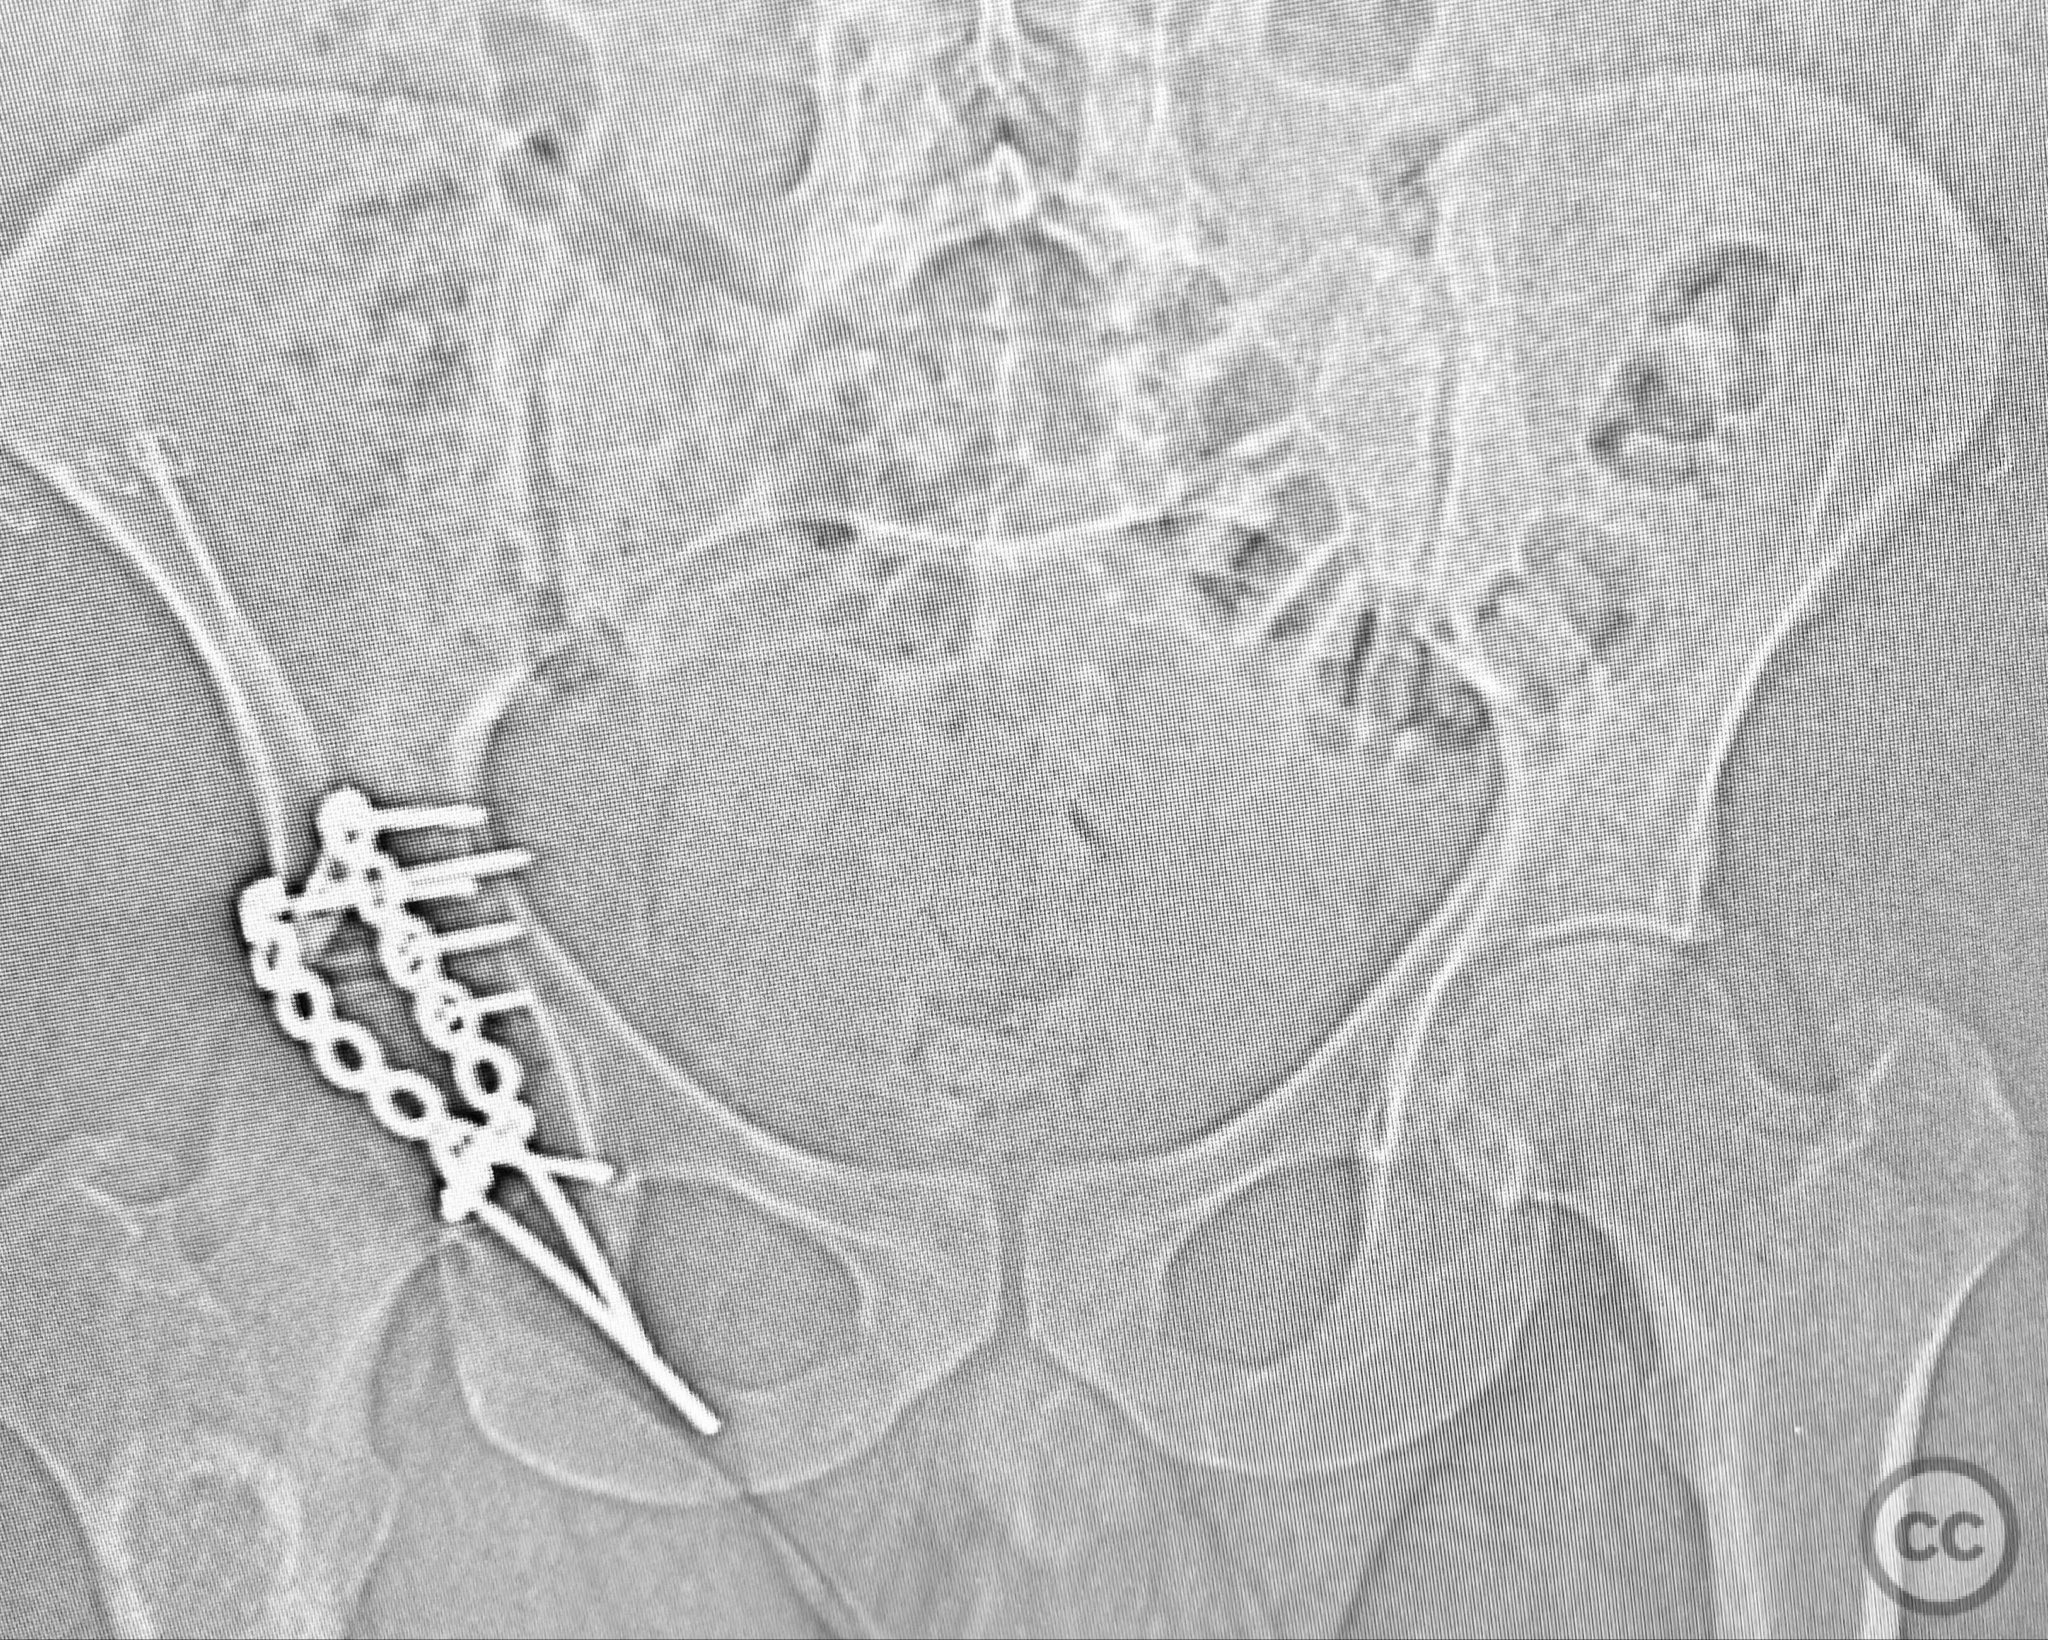

Anatomical surgical approach:  A standard Kocher-Langenbeck approach was performed: a longitudinal incision centered over the greater trochanter, extending proximally along the posterior iliac crest and distally along the femoral shaft. The fascia lata was incised, and the gluteus maximus split in line with its fibers. The short external rotators and piriformis were identified, tagged, and released to expose the posterior column and wall of the acetabulum. The sciatic nerve was identified in the greater sciatic notch region; intraoperatively, it was found to be severely contused, displaced, and uniquely penetrated by a sharp posterior wall fragment. Neuroplasty was performed, freeing the nerve from impalement and surrounding scar tissue. The intra-articular fossa acetabuli fragment was extracted, anatomically reduced, and stabilized along with other posterior wall fragments. A spring hook plate was applied to secure the cranial wall fragment due to its size and comminution.

Operative remarks:

Intraoperatively, the sciatic nerve was found to be not only contused but also impaled by a displaced posterior wall fragment—a rare occurrence in acetabular trauma. Careful neuroplasty was required to release the nerve from direct bony penetration without further iatrogenic injury. Reduction of all articular fragments was achieved under direct visualization, with particular attention to restoring congruity of the acetabular rim and fossa. The use of a spring hook plate provided necessary buttress for the large cranial wall fragment, which could not be adequately stabilized with standard plating alone.

Orthopaedic implants used:   3.5mm reconstruction plate, spring hook plate